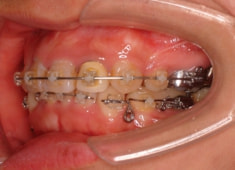

治療開始から1年8ヶ月後